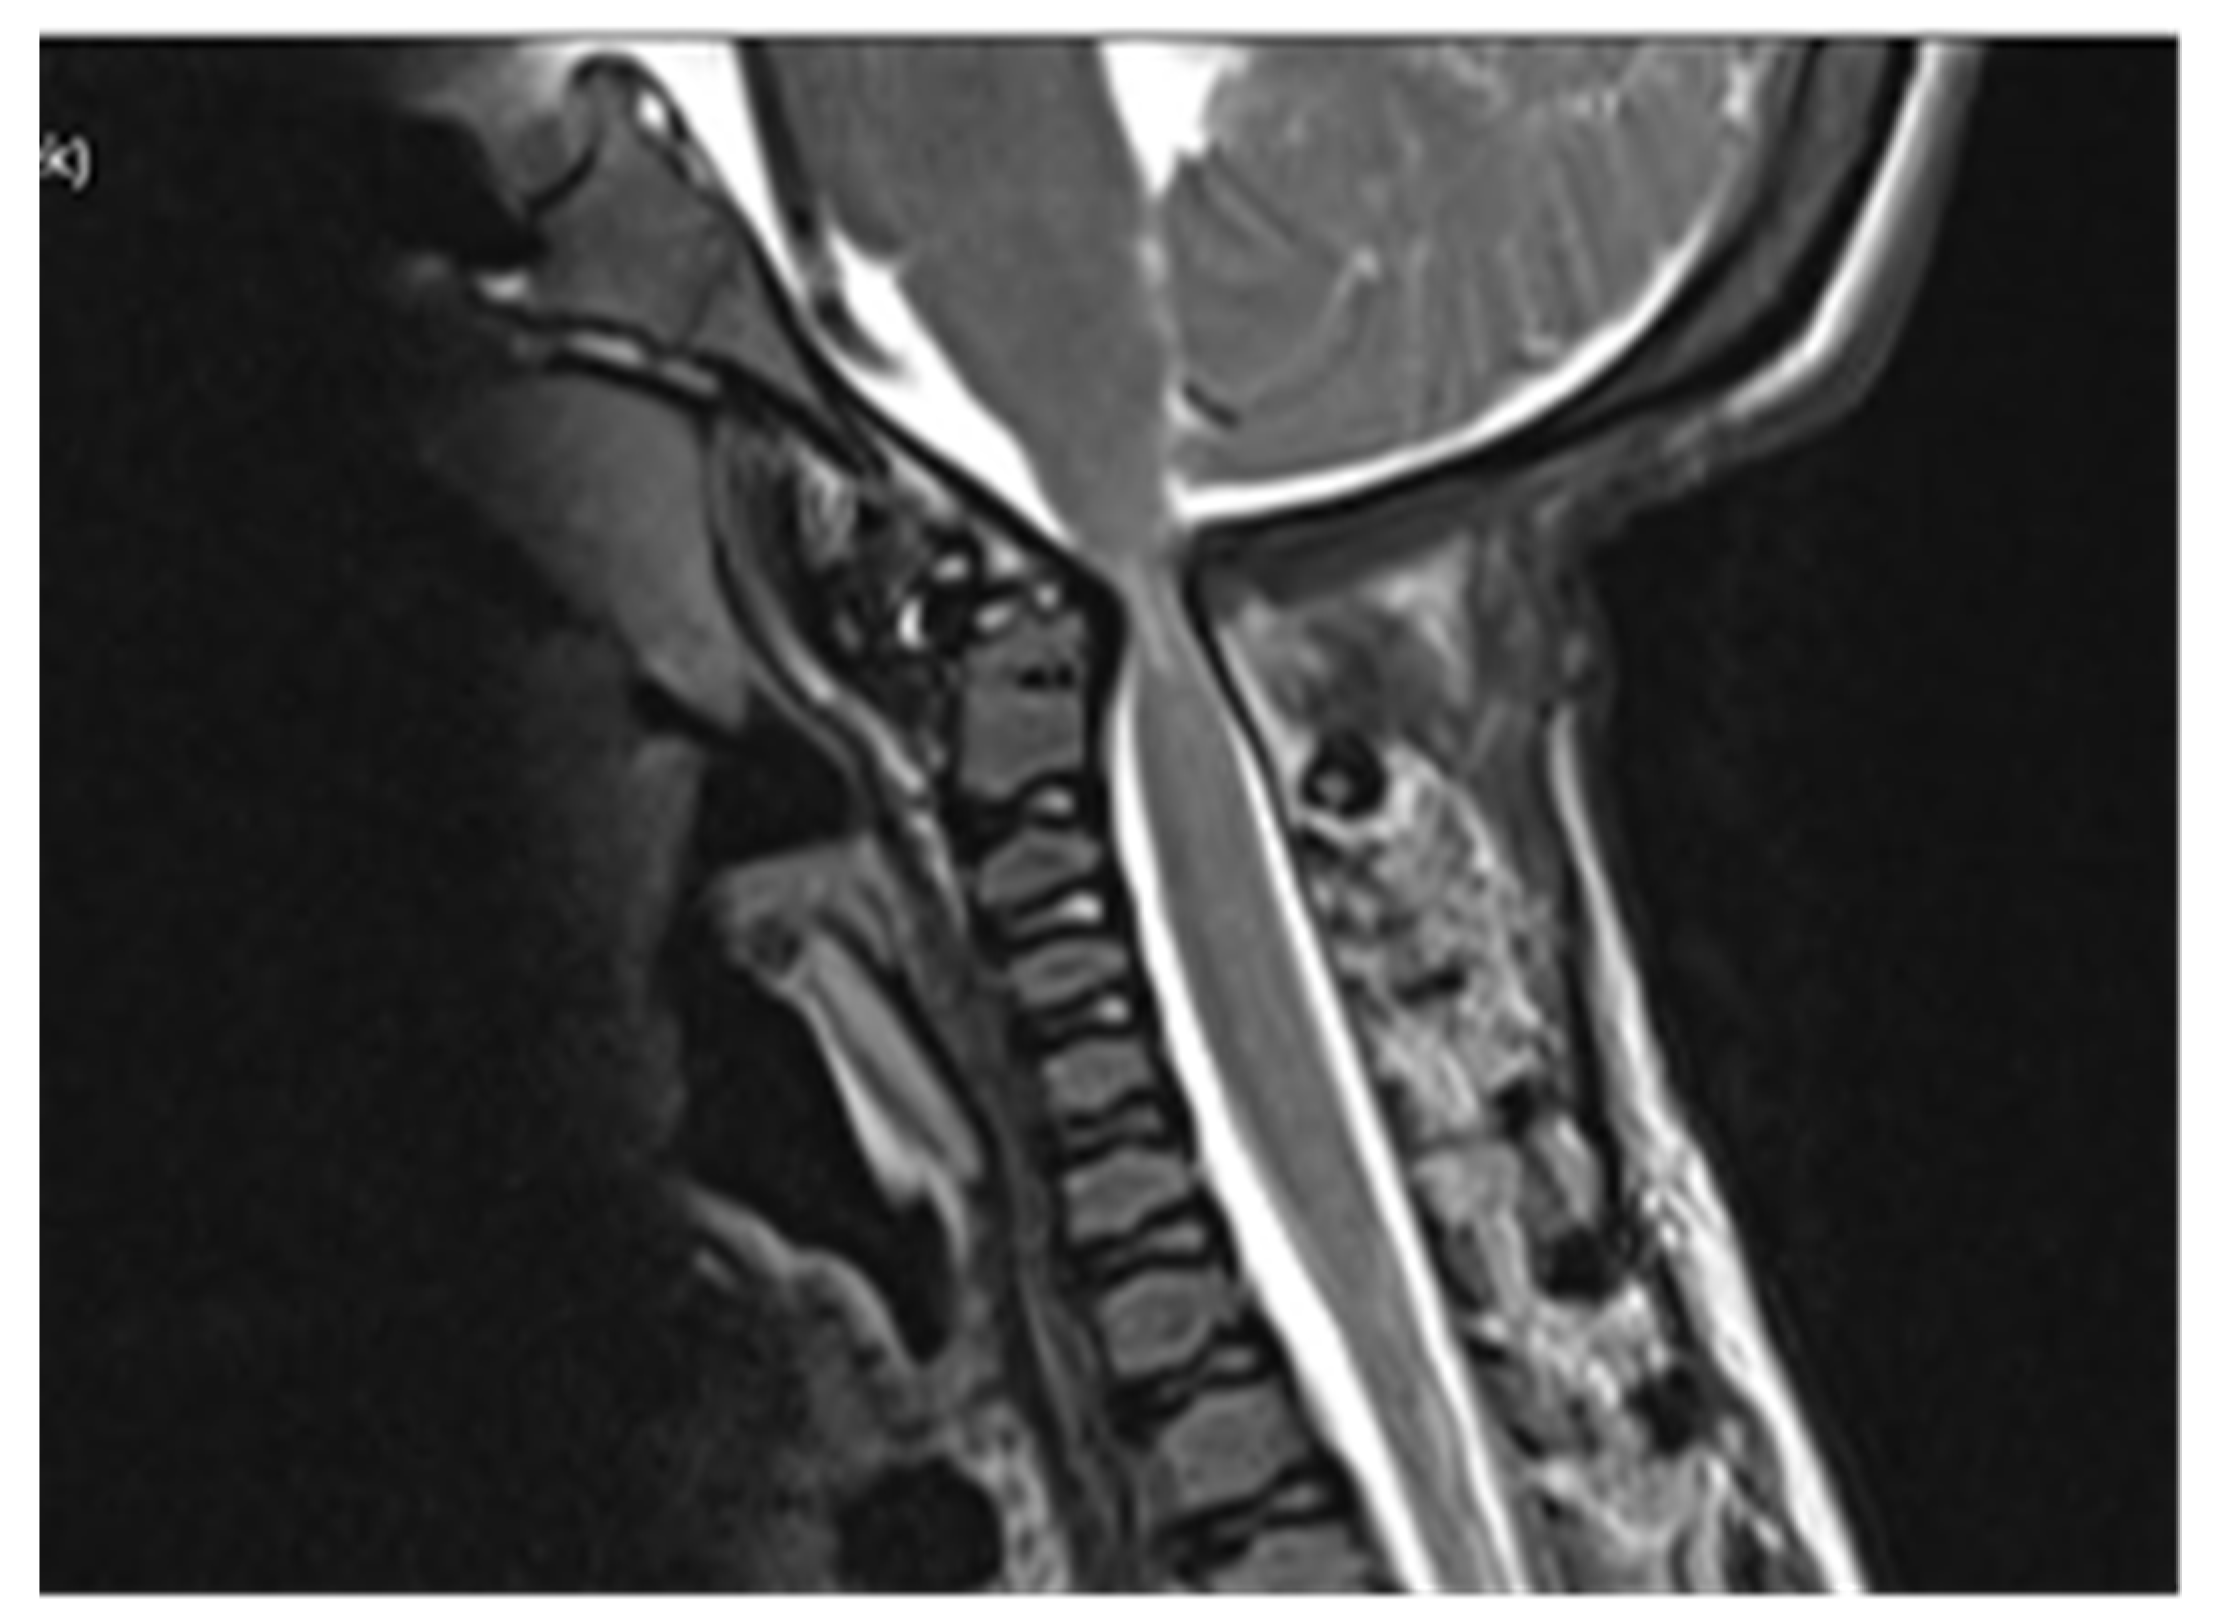

Computed tomography (CT) scan of cranio-cervical junction revealed bifid arch of the atlas as a part of skeletal disorders. Additional preoperative magnetic resonance imaging (MRI) revealed a critical stenosis of cranio-cervical junction with concomitant myelopathy (Figure 3).

A preoperative magnetic resonance imaging (MRI) scan revealed a severe myelopathy at the level of cranio-cervical junction and radiologic signs of atlanto-axial instability. Therefore, the authors decided to obtain only bone decompression of the foramen magnum and C1 vertebra to prevent any possible neurological deterioration with the aim of achieving a better radiologic outcome, e.g., partial or nearly complete regression of myelopathy. There were no radiological signs of platybasia and basilar invagination according to radiographic measurements of cranio-cervical junction.

Figure 3. Preoperative MRI scanning of cranio-cervical junction revealed critical stenosis and myelopathy, 14 years of age.